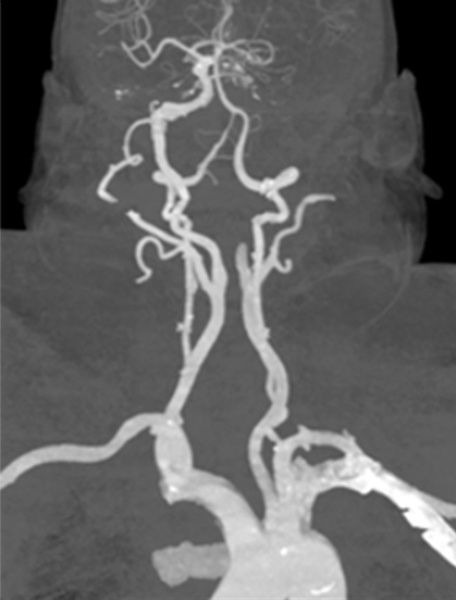

AngioCT - Internal carotid artery occlusion